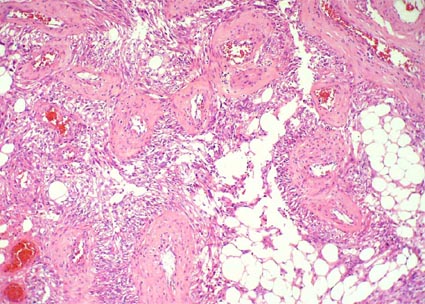

Hallazgos microscópicos: Es una lesión con características citológicas de bajo grado (grado 2 de Fuhrman) que mezcla áreas con aspecto tubular y sólido en medio de un estroma mixoide, con áreas sólidas fusocelulares. Previamente se clasificaba como "inclasificable" o "sarcomatoide" (aunque no es en realidad un cambio sarcomatoide, que implica alto grado). Las áreas tubulares presentan células cúbicas, con citoplasma débilmente eosinofílico, núcleos redondos, homogéneos, con nucléolo pequeño o no visible, poco pleomorfismo y escasas mitosis. Hay un estroma de aspecto mixoide o mucionoso (puede ser focal) que tiñe positivo con tinciones para mucinas ácidas. Las áreas fusocelulares muestran células con citoplasma y núcleos elongados, aspecto homogéneo, sin anaplasia, no hay características verdaderamente sarcomatoides, y escasas o ninguna mitosis identificable; estas áreas pueden ser similares a un leiomioma o a un sarcoma de bajo grado. La lesión es poco infiltrativa y no hay desmoplasia. En algunos casos hay áreas de necrosis focal, pero este hallazgo no se correlaciona con el comportamiento clínico del tumor, al menos en nuestros casos.

Figura 14. Carcinoma mucinoso tubular y de células fusiformes. Las células cúbicas se disponen formando túbulos irregulares en medio de un estroma con aspecto mucoide, basófilo (mixoide). Estas áreas se mezclan con áreas fusiformes. El grado nuclear suele ser 2 de Fuhrman, hay pocas mitosis y, en algunos casos, hay necrosis. Son lesiones poco metastatizantes. (H&E, X300).